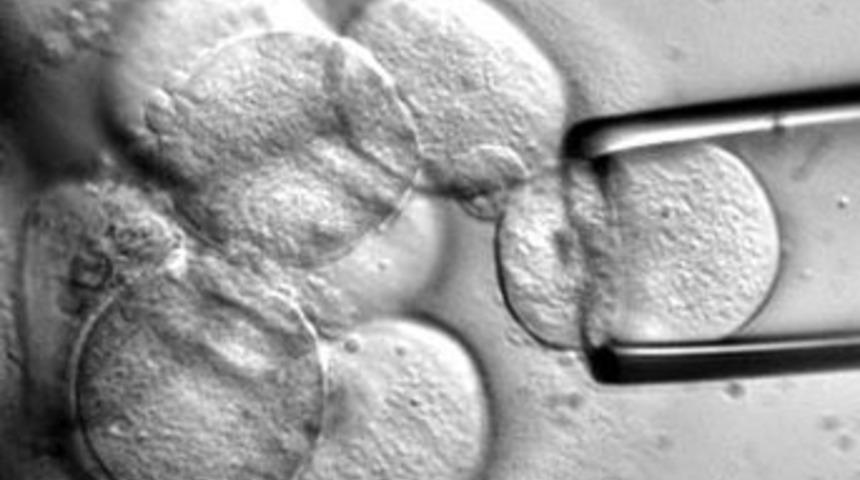

İstanbul Üniversitesi Cerrahpaşa Tıp Fakültesi Ortopedi ve Travmatoloji Ana Bilim Dalı Öğretim Üyesi Prof. Dr. Işık Akgün ve ekibi, Türkiye`de ilk kez kıkırdak tedavisinde ``kök hücre'yi kullanmaya başladı. Ekip, 1,5 ayda 9 kişiyi sağlığına kavuşturdu.

`Ancak bu kondrosit kültürleri yaratmaya üçüncü jenerasyondan başladık. Hastalardan biyopsi ile aldığımız kıkırdakları ATİye gönderdik. Burada yaklaşık 3 ila 5 hafta içinde hücreler üretildi. Bu hücreler özel üç boyutlu, jel kıvamında, istenilen şeklin verileceği yumuşaklıkta bir materyal olan skafolda emdirildi. Ameliyathaneye getirilen skafoldlar, 72 saat içinde hastaya uygulandı.

Ameliyathanede hastanın problemli eklemini - ayak bileği, kalça, omuz veya diz olabilir - açıyoruz. Kıkırdağın olmadığı bölgeye, bu skafoldu aynı ebatlarda keserek uyguluyoruz. Bu uygulamada bazen dikiş koyuyoruz, bazen yapıştırıcı kullanıyoruz. Daha sonra 6 ila 8 hafta hareketleri serbest bırakarak, basmama ya da destekli basmayla hastayı izliyoruz. Burada orijinal kıkırdak hücreleri ile vücuttaki orijinal kıkırdağa yakın kıkırdak oluşuyor. Bu yöntem bütün dünyada uygulanıyor. Türkiyede yeni uygulanmaya başladı. Sonuçlarını hep beraber göreceğiz. Bizim Türkiyedeki şanssızlığımız bu işe çok yeni başlamak. Ama bu başlama da hızlı gideceğimizi gösteriyor.``

Akgün, yöntemin bugüne kadar 9 hastaya uygulandığını ifade ederek, kök hücre yöntemini 15-45 yaş arasındaki kişilere ve 2 santimetrekarelik eksikliklerde uyguladıklarını bildirdi.